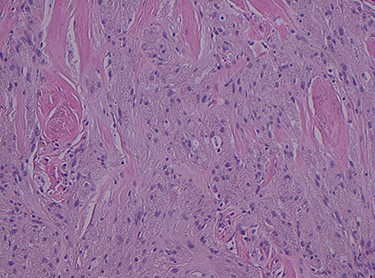

Histopathology of the right hemicolon found five firm nodules in the caecum and an additional seven polyps in the ascending colon macroscopically. Microscopically, a total of eight lesions in the caecum and ascending colon were found to be GCTs, varying in size from 1 to 7 mm. They were submucosal with intact covering mucosa (Figs 1 and 2). Tumour cells had periodic acid-Schiff (PAS)-positive granular cytoplasm and small nucleoli (Fig. 3). Immunohistochemical staining was positive for S-100 (Fig. 4) and inhibin. Twenty-four lymph nodes identified showed no abnormality. Spindling was seen in some tumours in this case, but overall, there are less than three worrisome features, and as such, these GCTs were considered atypical. Other polypoid lesions identified included two hyperplastic polyps and a submucosal lipoma.